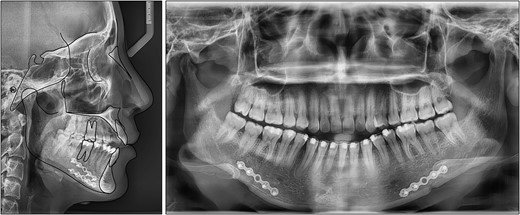

After treatment, class I canine and molar relationships were obtained on both sides with a normal overjet and positive overbite (Fig. 5). The posttreatment lateral cephalometric evaluation showed an improvement in both anteroposterior (point A-nasion-point B angle, 3.1°) and vertical dimensions (Frankfort mandibular angle, 31.0°). The posttreatment panoramic radiograph showed adequate root parallelism without any sign of root resorption (Fig. 6). The lateral cephalometric superimpositions confirmed the intrusion of the maxillary molars, the extrusions of the incisors, and the counter-clockwise autorotation of the mandible (Fig. 7).